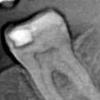

Лара3 Опубликовано 9 сентября, 2013 Автор Поделиться Опубликовано 9 сентября, 2013 Здравствуйте. Правда к сожалению, рентген не показывает пломбы с передней стенки, так что этот снимок все равно что ничего(( На жевательной поверхности зуба и на боковой, которые видны - старые пломбы - они как раз стоят нормально и не беспокоят. Ссылка на комментарий

juli63 Опубликовано 9 сентября, 2013 Поделиться Опубликовано 9 сентября, 2013 Прилегание той пломбы, что на снимке видно- плохое, есть патологический процесс под ней, да и на контактной поверхности скрытый кариес. По мне, так -это 'мартышкин труд' Ссылка на комментарий

Лара3 Опубликовано 12 сентября, 2013 Автор Поделиться Опубликовано 12 сентября, 2013 (изменено) Прилегание той пломбы, что на снимке видно- плохое, есть патологический процесс под ней, да и на контактной поверхности скрытый кариес. По мне, так -это 'мартышкин труд'это скорее всего помеха рентгена, вот еще 1 снимок - там все в норме. к тому же к этой пломбе нет претензий и не было. Изменено 12 сентября, 2013 пользователем Лара3 Ссылка на комментарий

juli63 Опубликовано 12 сентября, 2013 Поделиться Опубликовано 12 сентября, 2013 Кариес скрытый у вас там. Снимок плохого качества. Ссылка на комментарий